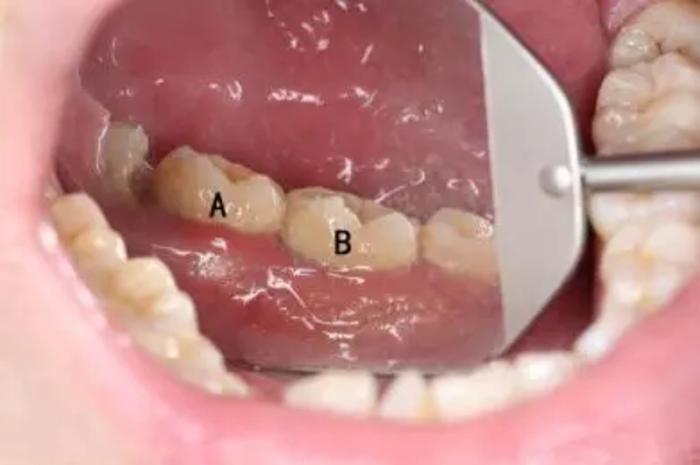

举个例子就知道啦!下图标注的A、B两颗牙齿表面看上去都没什么特别严重的问题

但是其中脱落的B牙却是这样的:

估计很多人都觉得不可思议,觉得这两颗牙看着都没那么脏啊?看着不脏,龈下却已经积满牙结石。